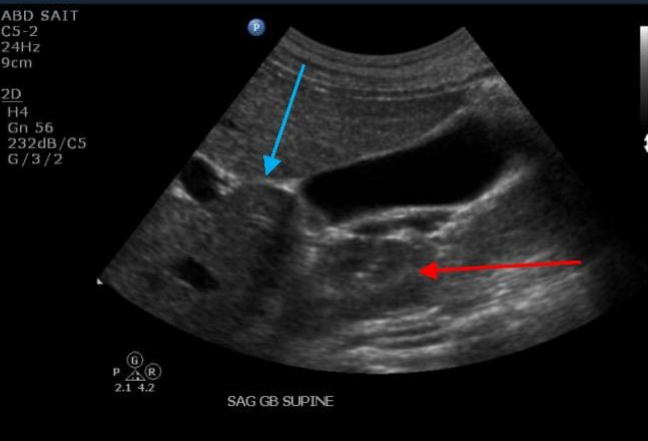

Label the Blue and red arrows

Blue: Portal confluence

Red: SMA